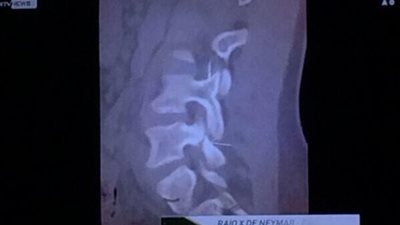

تنشر «فيتو» صورة ضوئية من أشعة الرنين المغناطيسي، التي خضع لها نيمار دا سيلفا مهاجم المنتخب البرازيلي ونادي برشلونة، عقب إصابته في مباراة كولومبيا، والتي انتهت بفوز البرازيل 1/2 وتأهله للدور نصف ...